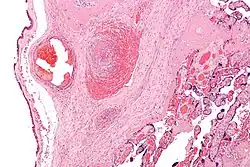

It can be diagnosed by histomorphologic examination of the placenta and is characterized by fetal vessel thrombosis and clustered fibrotic chorionic villi without blood vessels.

Low mag.

High mag.